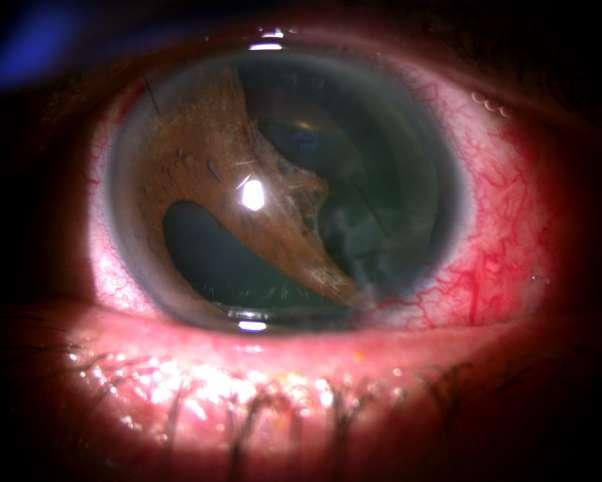

Caso aportado por Dr. Cristian Sanchez

Hombre 53 años con anteccedentes de facoemulsificación + implante de lente OD, consulta tras episodios de uveitis hipertensiva a repetición asociados a hifema del ojo derecho.

ü AV 0.7 OD

ü PIO OD: 28mmHg

ü BMC (Imagen A y B): Córna transparente, cámara anterior formada, Tyndall +, LIO in situ, transiluminación sectoriales del iris, iridotomías superior e inferior. Nevus conjuntival.

UVEÍTIS - GLAUCOMA - HIFEMA

8.C. SÍNDROME

A B

ü Gonioscopía (Imagen C): Ángulo abierto en en 270º, trabéculo con pigmento, SAP inferior

ü Fondo de ojo (Imagen D): Papila pálida con excavación 0.9. macula sana

ü El Sd. UGH es una complicación que puede aparecer en el post operatorio (precoz o tardío) luego de la implantación de un lente intraocular.

ü Se define clásicamente por la triada que su nombre comprende, aunque pueden aparecer formas incompletas.

ü La incidenccia se ha visto aumentada debido al incremento de la cirugía de cristalino, ya sea por catarata o con finalidad refractiva.

ü La patogenia se debe a la presión ejercida por los hápticos del lente intraocular (LIO) sobre el tejido uveal y puede presentarse en paciente con lentes en cámara anterior, sulcus o saco.

ü Sospechar en paciente pseudofáquico con episodios recurrentes de uveitis no filiada C D